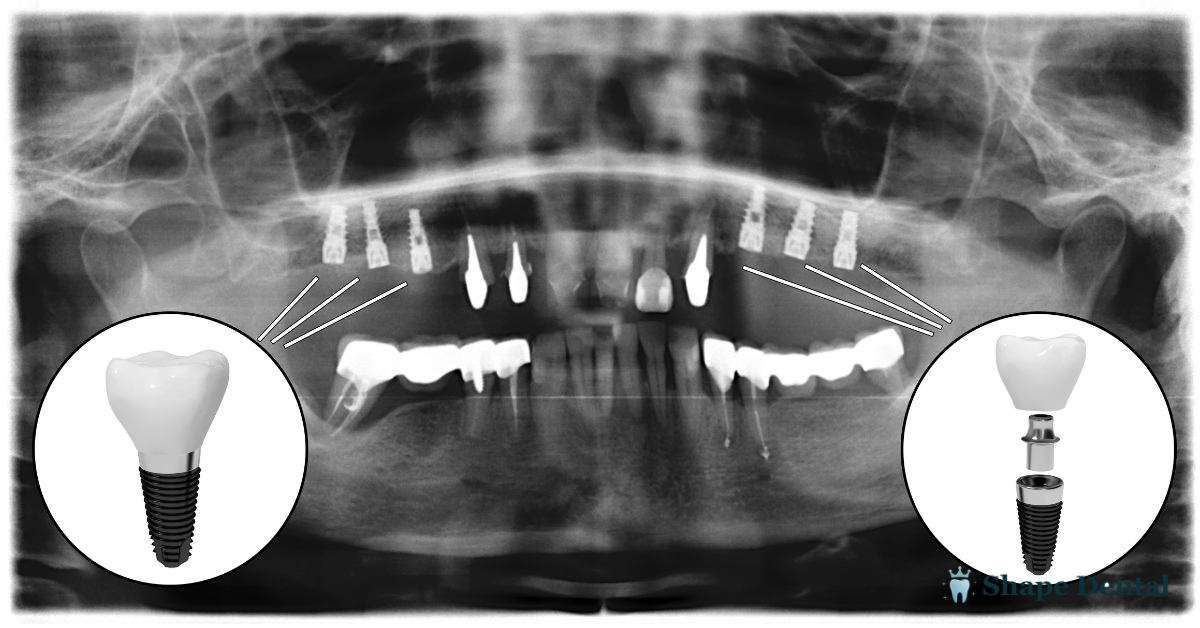

An all-on-4 dental implant treatment involves placing four strategically positioned implants in the jawbone to support a full set of replacement teeth. Two implants are placed in the front, while two are angled in the back to support the implants where bone density is often stronger.

This dental implant procedure is often recommended for patients with missing teeth who may not qualify for individual implants. While the benefits of all-on-4 include stability and efficiency, proper implant placement and planning are critical to long-term success.